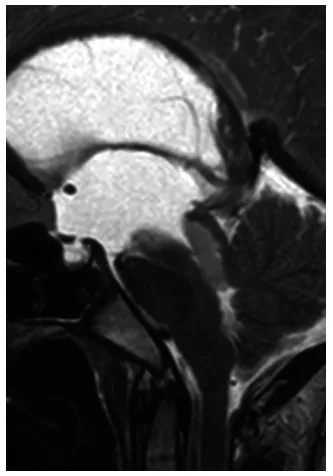

MRI检查结果出来的那一刻,我腿都软了。医生说孩子第三脑室后部有个从中脑顶盖长出来的强化病灶,正好堵住了中脑导水管这个脑嵴液循环的通道,已经形成了梗阻性脑积水(图1)。

图1.矢状位T2加权MRI显示第三脑室后部导水管入口处病灶。